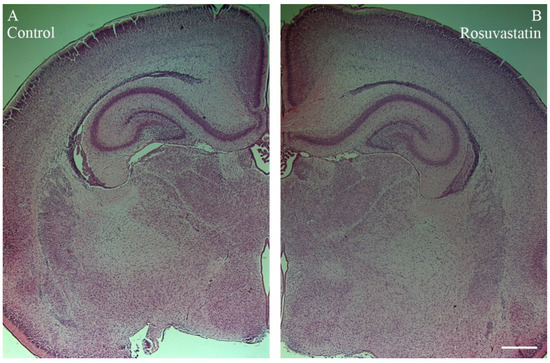

2.2. Prenatal RST Exposure Does Not Affect Cell Composition in the Newborn Brain